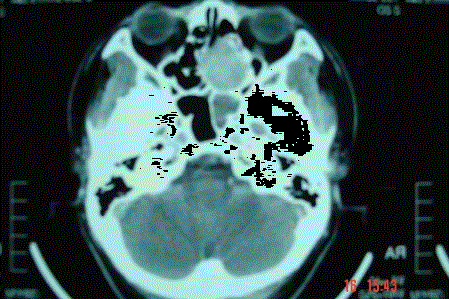

问题 病历摘要: 患者男,37岁,因右鼻塞伴涕中带血4个月入院,患者4个月前始右鼻塞,为间断性,偶有涕中带血,时有流脓性分泌物,并症状渐渐加重。但发病以来患者无头痛、面部麻木和疼痛,无复视及流泪,张口正常。检查:右侧鼻腔总鼻道可见表面光滑、质中、粉红色肿物,触之不易出血。鼻咽黏膜光滑,未见新生物和黏膜糜烂。颈部未及淋巴结肿大。 鼻腔鼻窦恶性肿瘤有哪些手术疗法?